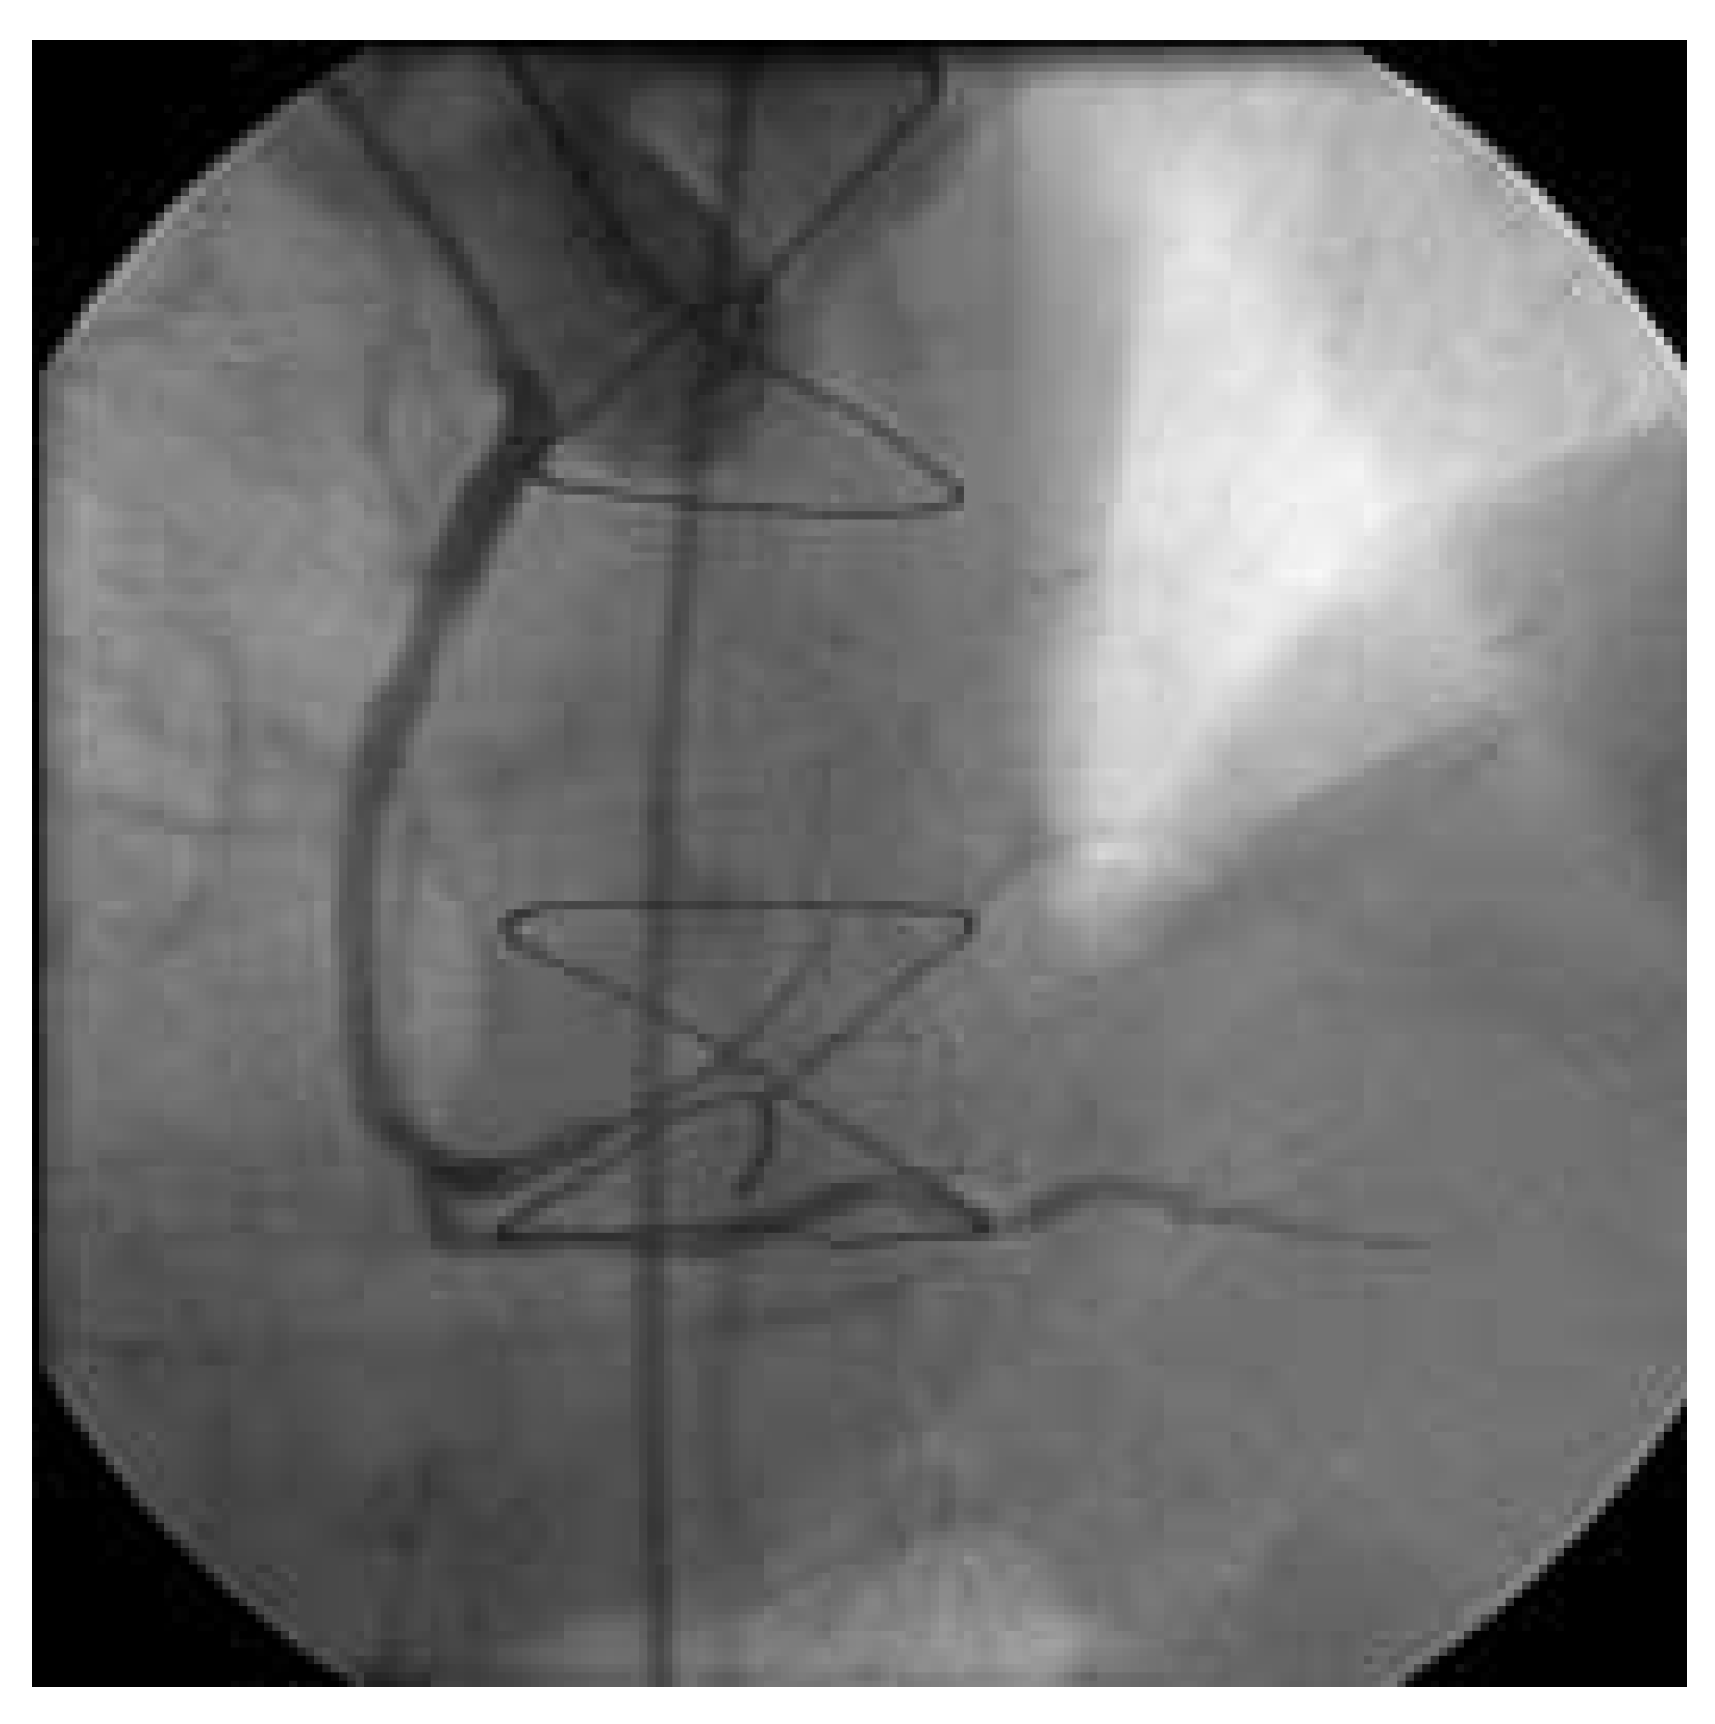

Abbildung 7. Nach Thrombus-Aspirationskatheter kommt der Venenbypass zur Darstellung (hier proximaler Abschnitt).

Abbildung 8. Fortsetzung des Venengraftes (Abb. 7) und Peripherie mit promptem Fluss.

Beim zweiten Patienten handelt es sich um einen 72jährigen Patienten, welcher sich 1980 erstmals einer Bypass-Operation unterzog. 1988 wurde er reoperiert (LIMA zu RIVAund Diagonal-Ast, RIMA auf PLA des Ramus circumflexus, Vene zum RIVP der RCA und zum 2. PLA). Nach einer Prostata-Radikaloperation im Sommer 2003 kam es zu einer progredienten Angina pectoris CCS III. Trotz voll ausgebauter antiischämischer Behandlung traten immer häufigere Episoden von Ruhe-Angor auf. Im Februar 2004 zeigte die Koronarangiographie einwandfreie arterielle Bypass-Verhältnisse und einen proximalen, langstrekkigen Verschluss des Venengraftes (Abb. 5). Nach Drahtpassage und mehrfacher, langstreckiger Ballondilatation und intravaskulärer Nitrat-Gabe kommt kein antegrader Fuss zustande (Abb. 6). Erst nach mehreren Passagen mit dem Thrombusaspirationskatheter kommt der Venenbypass und die angeschlossenen Gefässe zur Darstellung. Das Endresultat nach Stenteinlage (Abb. 7 und 8) ist sehr zufriedenstellend. Der Patient ist seit dem Eingriff beschwerdefrei.